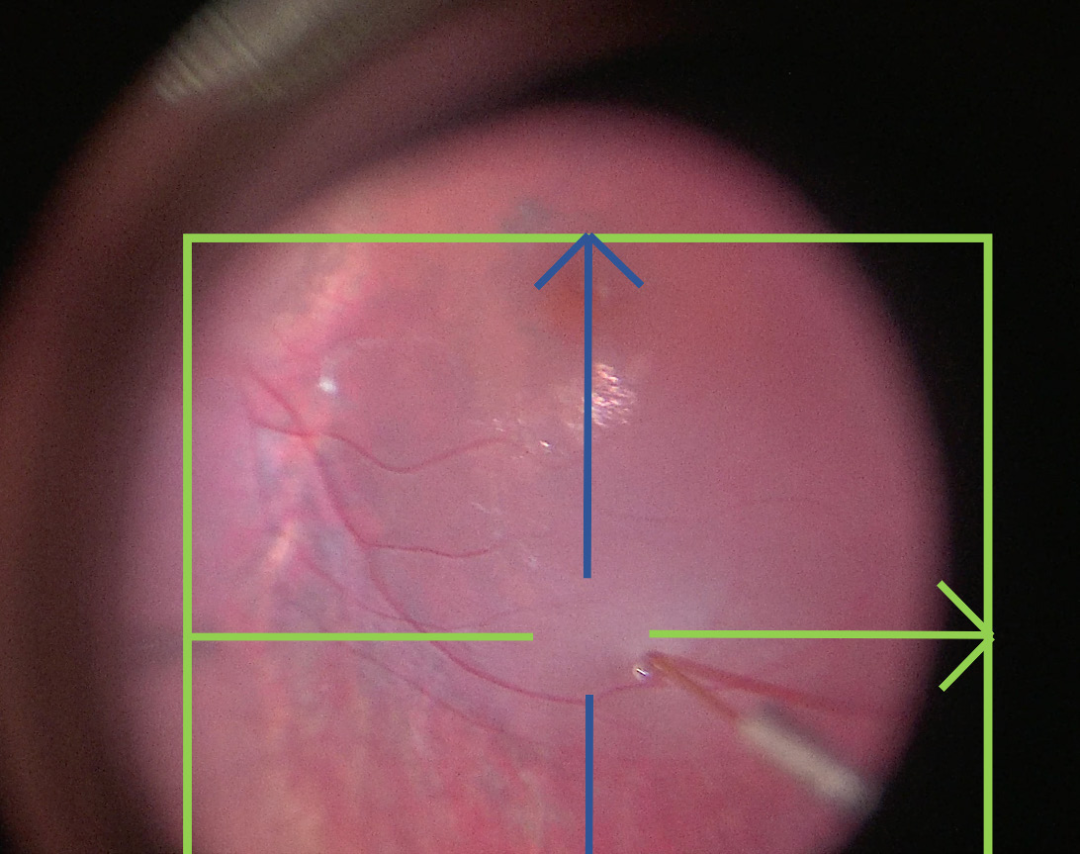

視網(wǎng)膜下注射基因療法的外科技術(shù)在技術(shù)上要求很高,具有挑戰(zhàn)性,因?yàn)樵诒O(jiān)測(cè)泡狀出血形成和傳播的液體分布時(shí),識(shí)別套管深度和穿透是困難的。16-18外科醫(yī)生的手必須穩(wěn)定,并且在大約兩到五分鐘內(nèi)只進(jìn)行小的調(diào)整,同時(shí)變化注射壓力并使用腳踏板調(diào)整顯微鏡控制。可能的并發(fā)癥包括治療不足或不成功,載體從泡狀出血中逸出,或外科創(chuàng)傷。治療不足可能發(fā)生在未能傳遞全部載體量,未能覆蓋所需的治療區(qū)域,或?qū)⑤d體傳遞到錯(cuò)誤的眼內(nèi)層(例如脈絡(luò)膜上而不是視網(wǎng)膜下)。當(dāng)擴(kuò)大視網(wǎng)膜切口,無(wú)意中在嘗試接合主要視網(wǎng)膜切開(kāi)口時(shí)創(chuàng)建第二個(gè)視網(wǎng)膜切口,或在創(chuàng)建多個(gè)泡狀出血時(shí)泡狀出血合并時(shí),會(huì)發(fā)生載體回流。當(dāng)高注射壓力對(duì)RPE或黃斑施加過(guò)大壓力,導(dǎo)致yongjiu性RPE變形或全層黃斑孔時(shí),會(huì)產(chǎn)生外科創(chuàng)傷。術(shù)中光學(xué)相干斷層掃描(術(shù)中OCT)提供了實(shí)時(shí)信息向外科醫(yī)生反饋,關(guān)于穿刺進(jìn)入后段結(jié)構(gòu)的深度,注射液體的分布和傳播,載體回流,以及在這些操作過(guò)程中黃斑的完整性。這提高了視網(wǎng)膜基因增強(qiáng)療法程序的安全性和治療傳遞的準(zhǔn)確性。